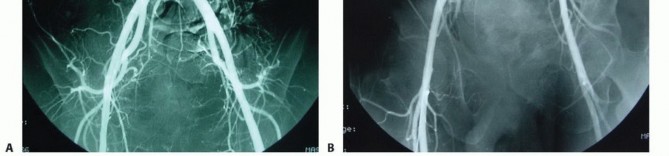

تصوير الأوعية الدموية

ضروري للأورام العجزية الخبيثة. يساعد في تحديد الإمداد الدموي للورم والهياكل الوعائية المحيطة لتقييم مخاطر الجراحة. يُعد الانصمام الانتقائي للأوعية الدموية المغذية للورم قبل الجراحة أمرًا بالغ الأهمية لتقليل فقدان الدم أثناء العملية.

- الانصمام الشرياني: يُوصى بالانصمام الشرياني (سد الأوعية الدموية المغذية للورم) قبل 12 إلى 24 ساعة من الجراحة لتقليل فقدان الدم.